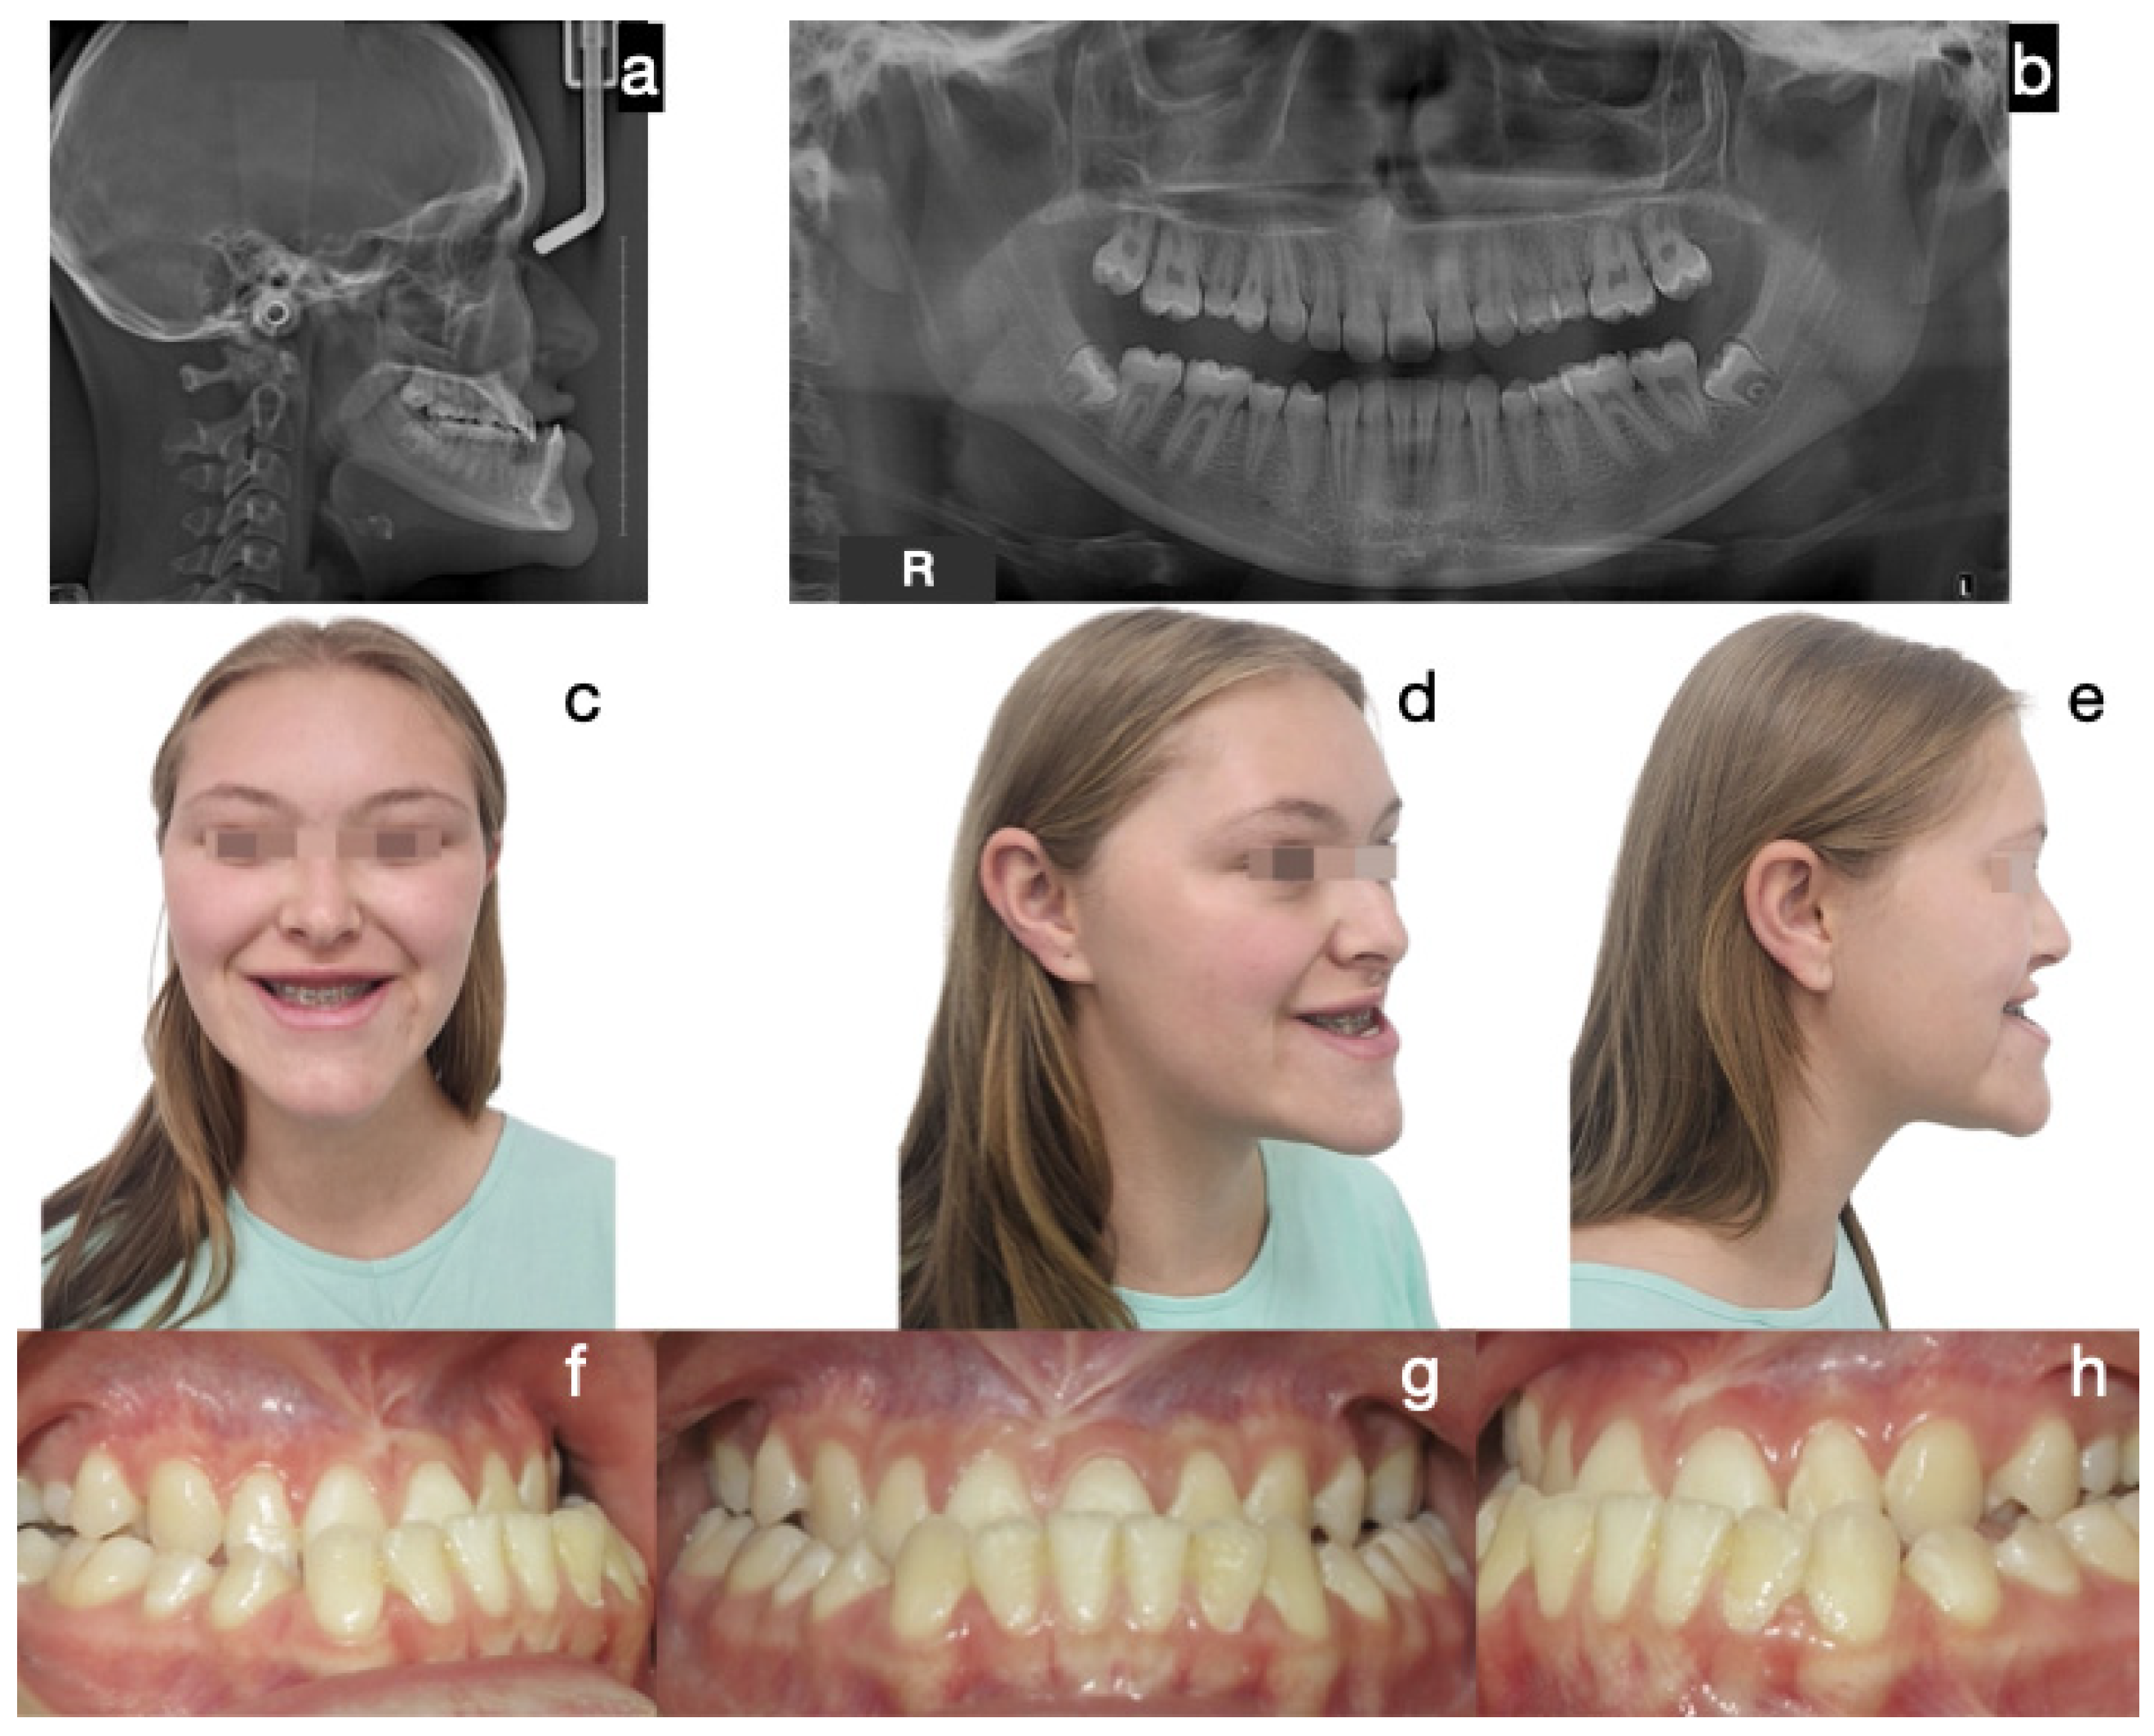

- Protocol C: Bilateral high condylectomy followed by maxillary orthopedics (if growth potential exists) or compensatory orthodontics. This approach is for patients with growth potential or mild conditions, where early detection allows for correction using only condylectomy and proper orthodontics without additional surgery (Figure 7, Figure 8, Figure 9 and Figure 10).

| 9 | 11 | F | Mandibular prognathism. Elongated and posterior divergent condyles. Accelerated mandibular growth after menarche (11 years). Edge-to-edge bite. Incisive compensation. No family history of Class III. | Right condyle: 1.45 Left condyle: 1.38 | Right condyle: 5 mm Left condyle: 5 mm | Soft condyle thickness. Right 0.6 mm. Left 0.6 mm. Positive findings for BCH. | Type C. Bilateral condylectomy, followed by skeletally anchored orthopedics, use of elastics with orthopedic forces and corrective orthodontics of the malocclusion. | 48 months |